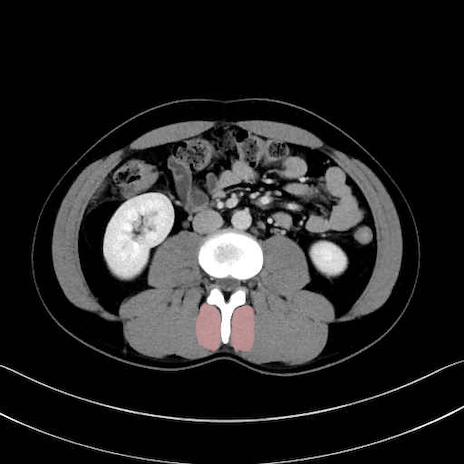

多裂筋 (Multifidus)